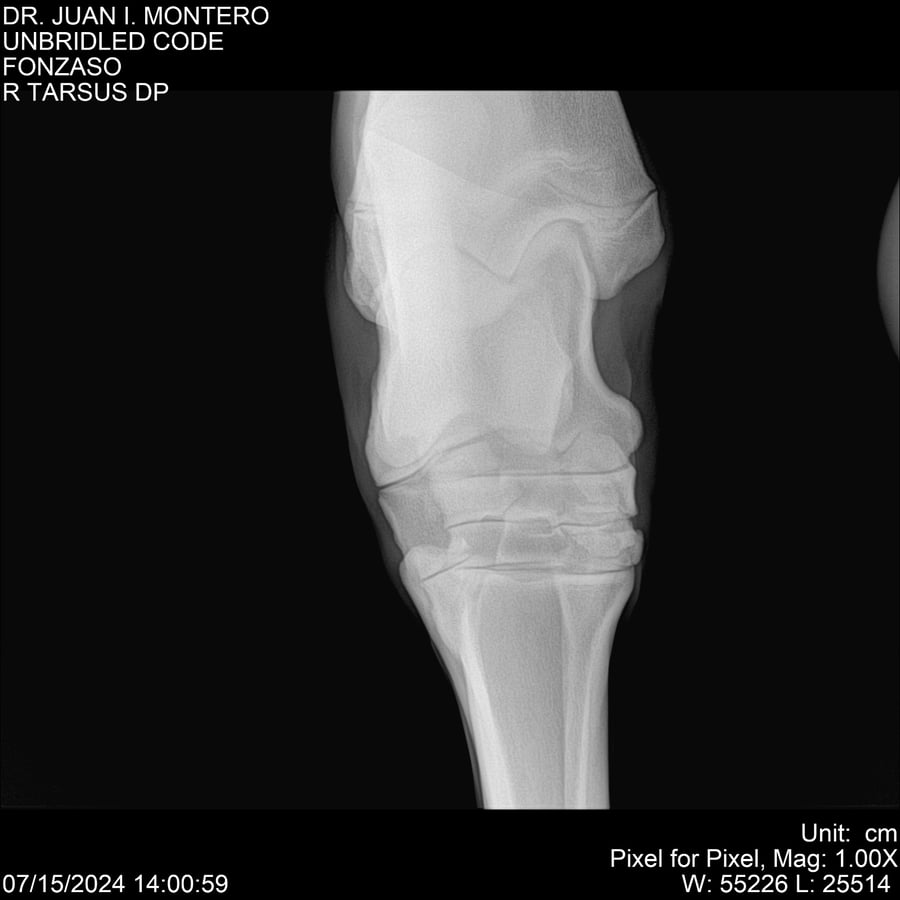

• Empresa: Abelenda N. R., Walter Hugo